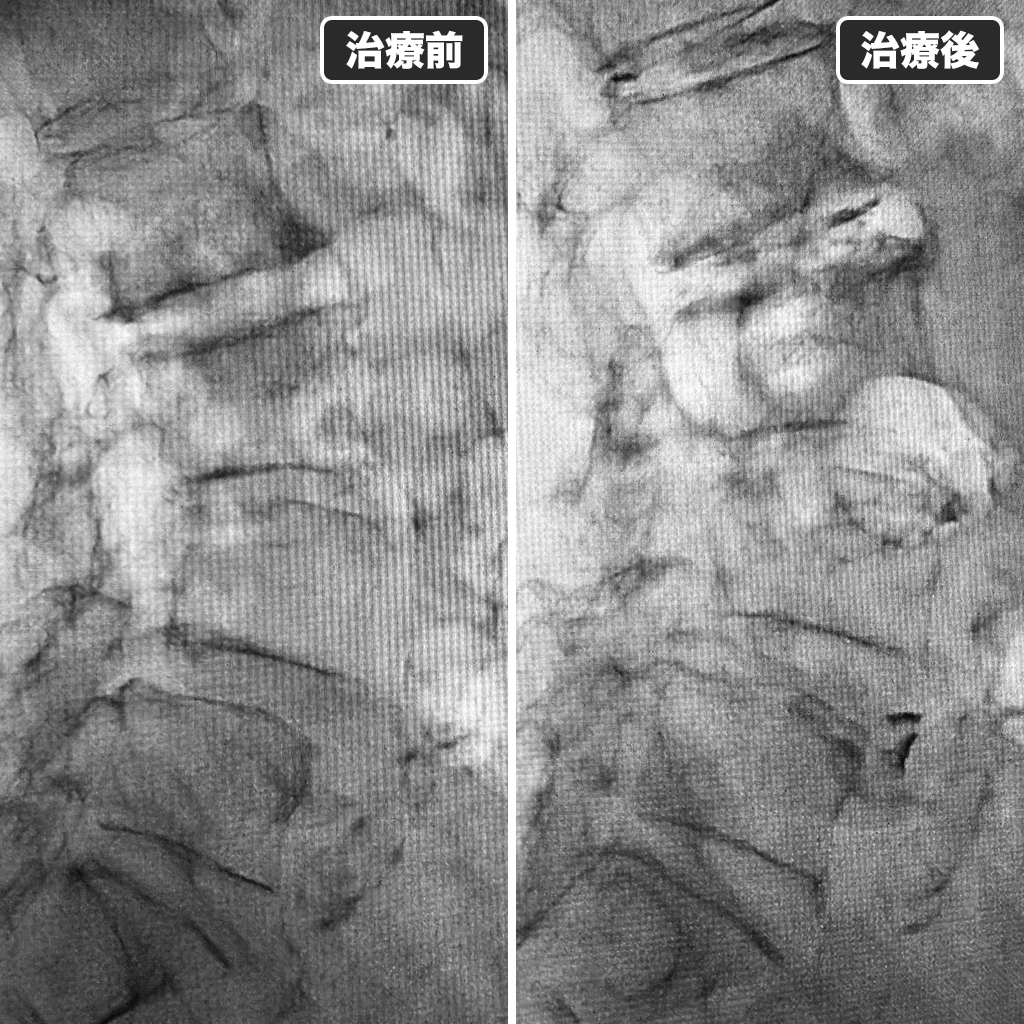

治療前後のレントゲン

治療前後のレントゲン写真です。左側が治療前、右側が治療後になります。最近は手術をされた後の患者様からのご相談も増えております。